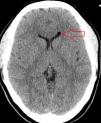

CT and MR images revealed 2 round shapes, located in the anterior and posterior areas of the left lateral ventricle, which were compatible with air bubbles (Figs. 1 and 2). MRI angiography of the intracranial vessels ruled out aneurysms, arteriovenous malformations, vertebral or internal carotid artery dissection, and venous sinus thrombosis. Our patient was diagnosed with thunderclap headache due to pneumocephalus secondary to an epidural block using the LORA technique. She received conservative treatment with analgesics and rest; symptoms resolved in a few days.